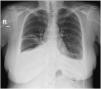

A chest radiograph revealed a small volume bilateral pleural effusion, which was larger on the right. A CT-Scan of the thorax was then performed showing a bilateral free-flowing pleural effusion, which was larger on the right, and a partial collapse of the right middle lobe with no clear obstructive cause. A flexible bronchoscopy provided better characterization with the finding of right middle bronchus tapering, allowing the progression of the bronchoscope. A bronchoalveolar lavage and brushing were performed in that bronchial segment, with no abnormalities found. An ultrasound-guided diagnostic thoracocentesis was performed, with the removal of 26 mL of pleural effusion with a hazy and milky appearance, classified as a lymphocytic predominant exudate. The pleural fluid was categorized as a chylothorax after the biochemical examination (pleural fluid triglyceride concentration of 375 mg/dL). The pleural fluid culture, immunophenotyping and cytology exam were negative. Liver function tests were normal.

A clinical suspicion of a Bosutinib induced chylothorax was raised. Since all the criteria for stopping TKI were met, Bosutinib was withdrawn, with a complete resolution of the bilateral pleural effusion within five weeks, therefore confirming the diagnosis. Respiratory symptoms resolved within a week. The patient remains in complete molecular response after 6 months without TKI therapy.